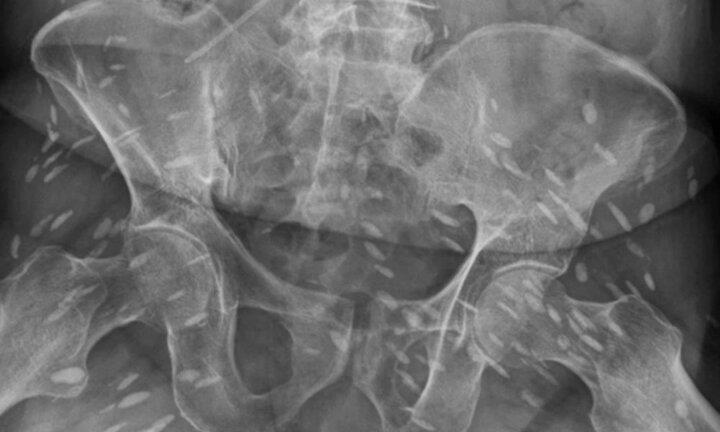

Sán làm tổ chi chít trong cơ thể người đàn ông 74 tuổi

Quá nhiều trứng sán trong người khiến não của người đàn ông bị ảnh hưởng, gây ra hiện tượng mất trí nhớ và đi lại khó khăn.